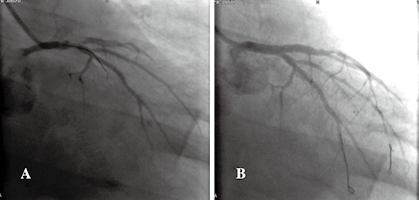

注:A PCI前 B PCI后

图5. 二次PCI术典型截图